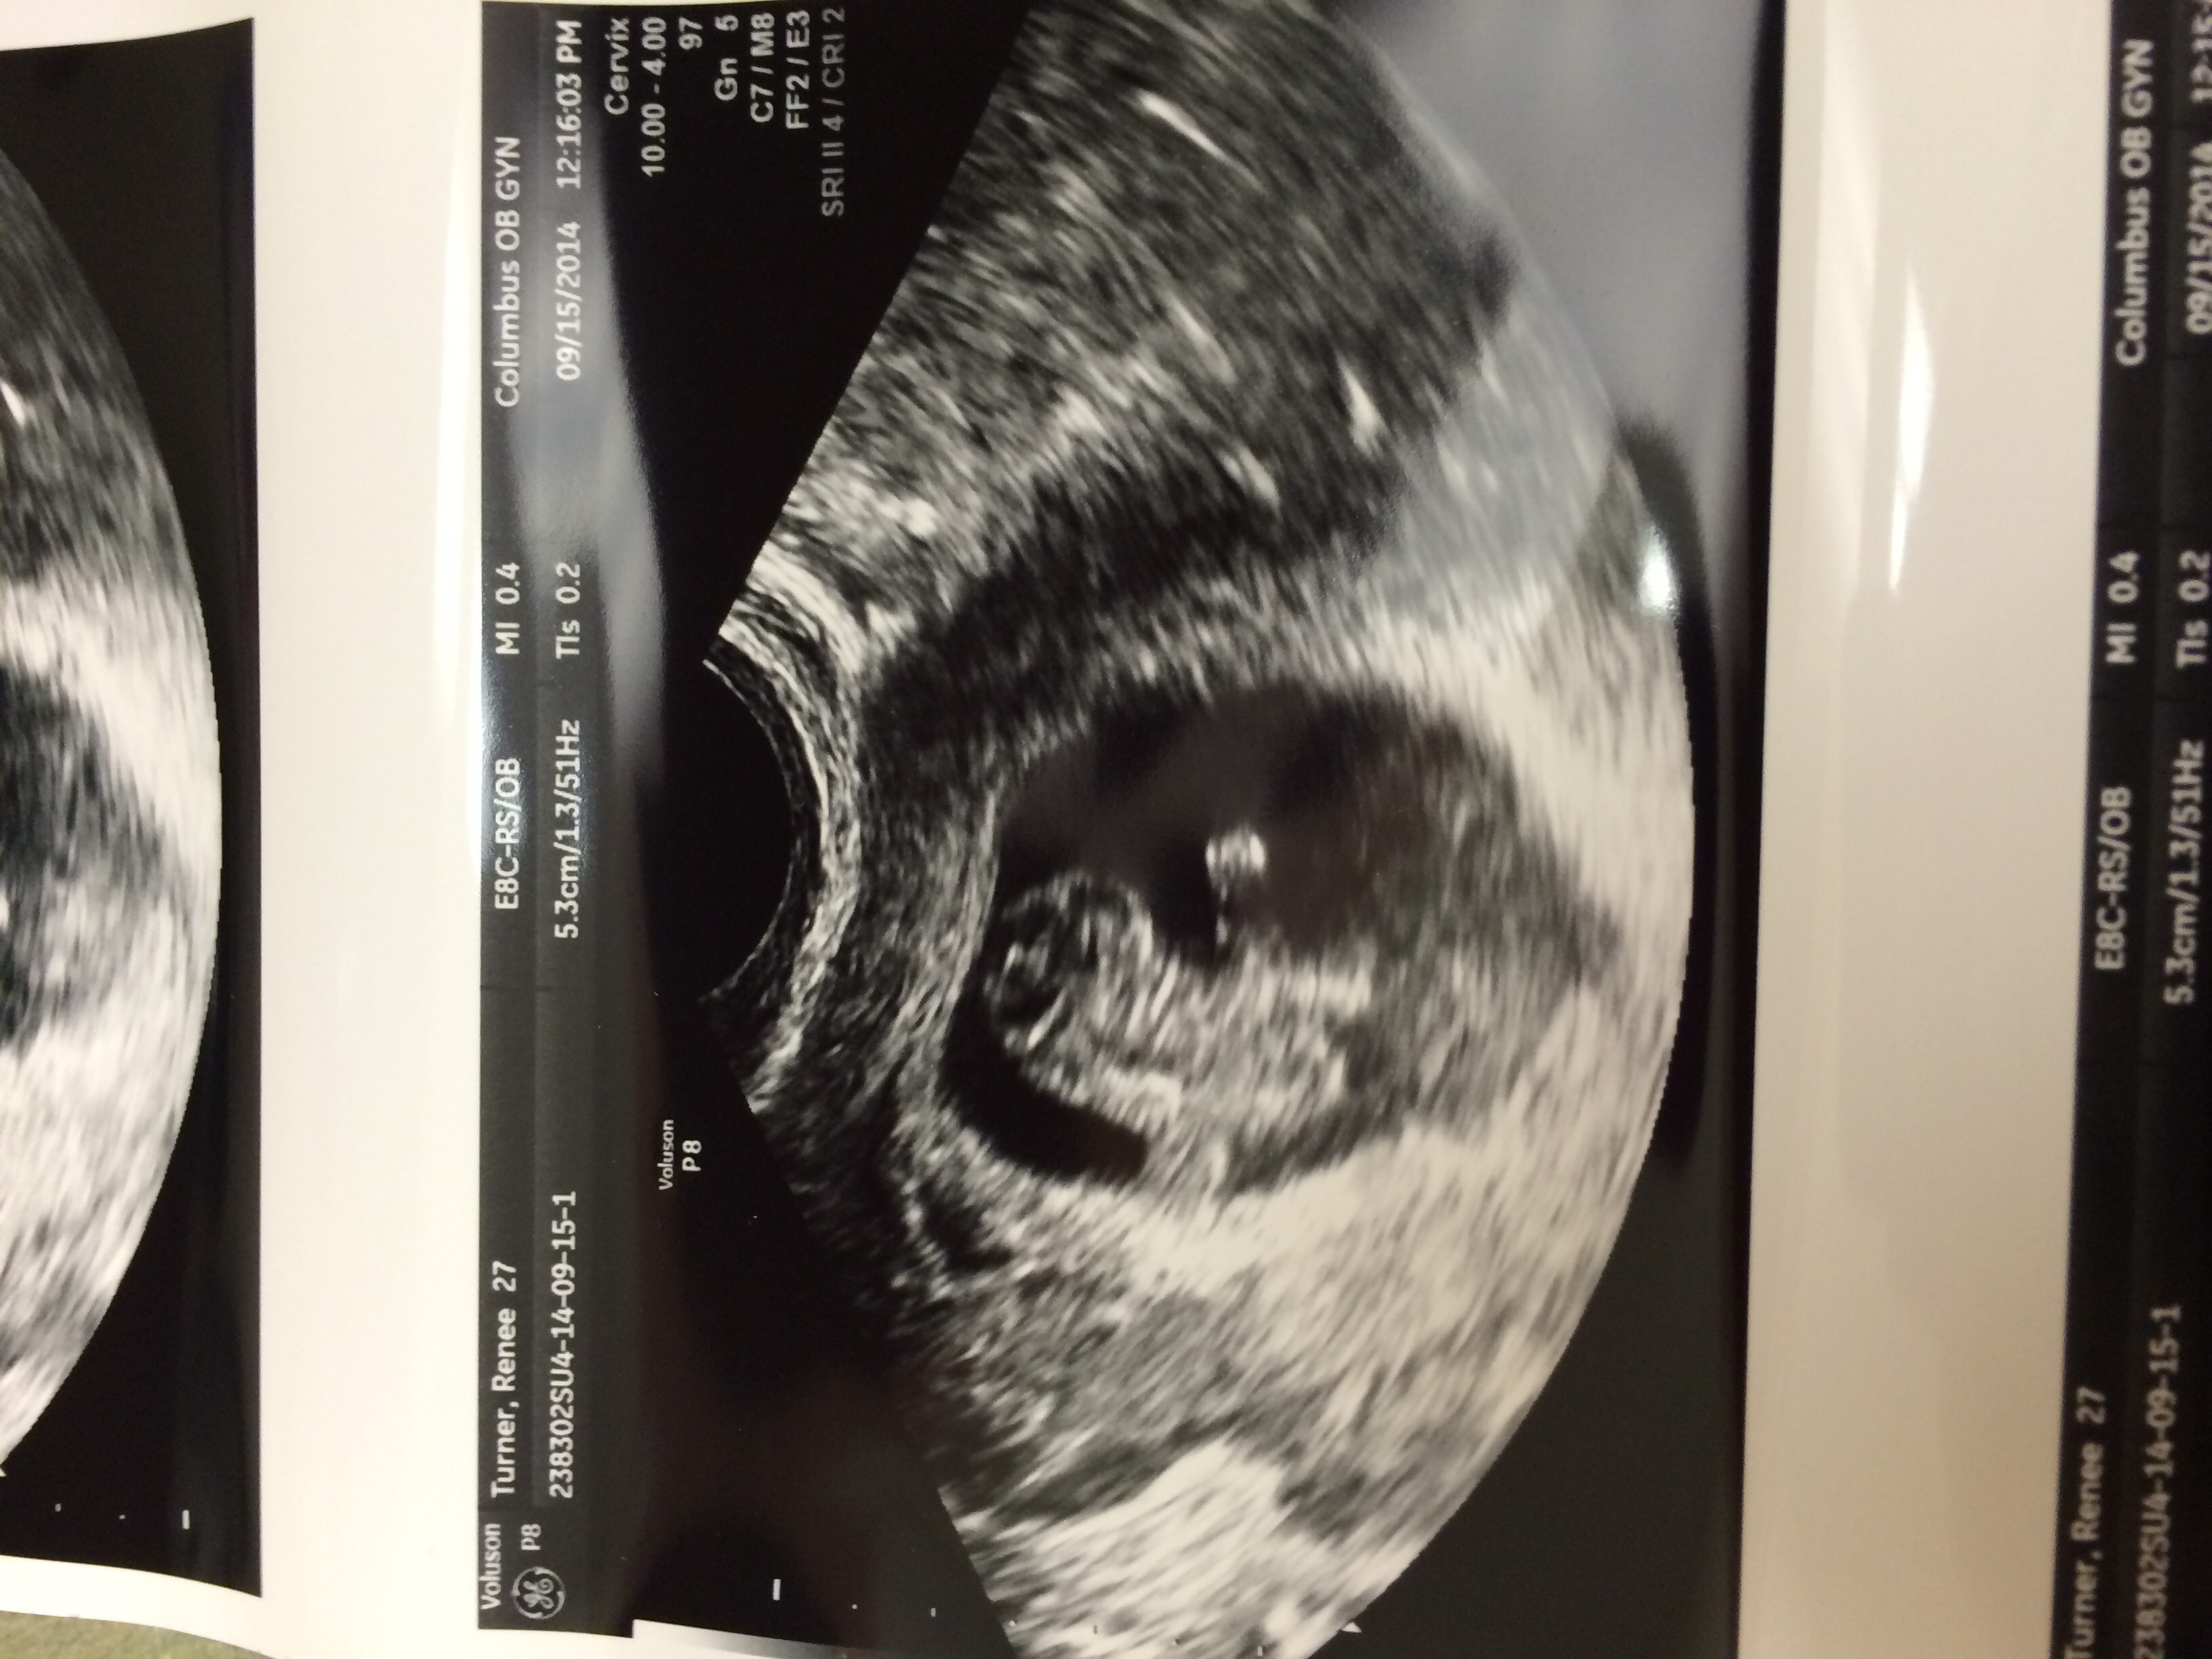

Anxiety ridden the last few days because of brown and red mucus/spotting but ultrasound showed a healthy 9 week baby and a strong heartbeat.

Next goal is get past 10w 5days when our last baby quit growing. We didn't find out until 12 weeks though. Dr is going to do a check at 11 weeks then go to normal appointments.